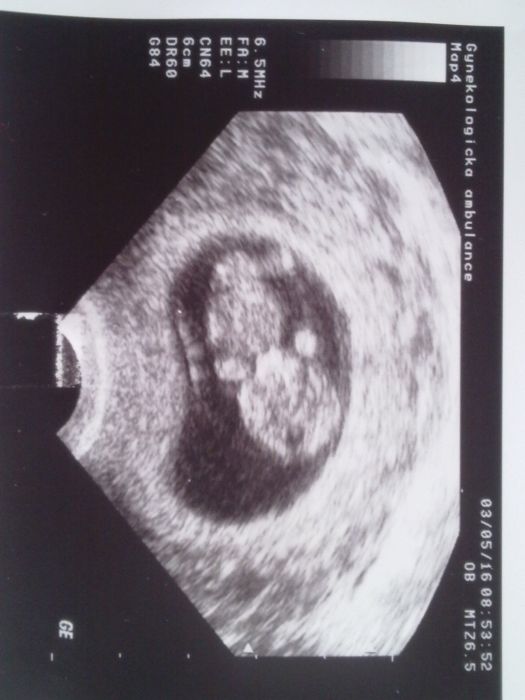

Ahoj holky, všechny vás zdravím a přidávám se do diskuze. Radostná zpráva se potvrdila, včera jsem byla u doktorky a jsem v 5+5 tt. Neskutečná radost. Bude mi totiž letos 41, mám doma už 2 děti 16 a 14 let. Je tady někdo taky již trochu starší? Ráda bych si třeba napsala .....

Za 14 dnů jdu na kontrolu, doufám, že srdíčko bude vidět a vše bude OK, z toho mám největší strach. Všem gratuluj ua držím palce.